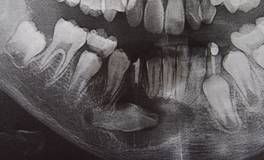

頜骨囊腫在X線平片上表現為圓形或卵圓形密度減低區,邊界清楚,邊緣光滑銳利,其內可以是單房或多房。隨著囊液積聚,囊腫具有一定的膨脹性,可引起臨近牙移位,少數可見牙吸收。周圍骨質吸收,囊腔壁為緻密白線(骨皮質線)。